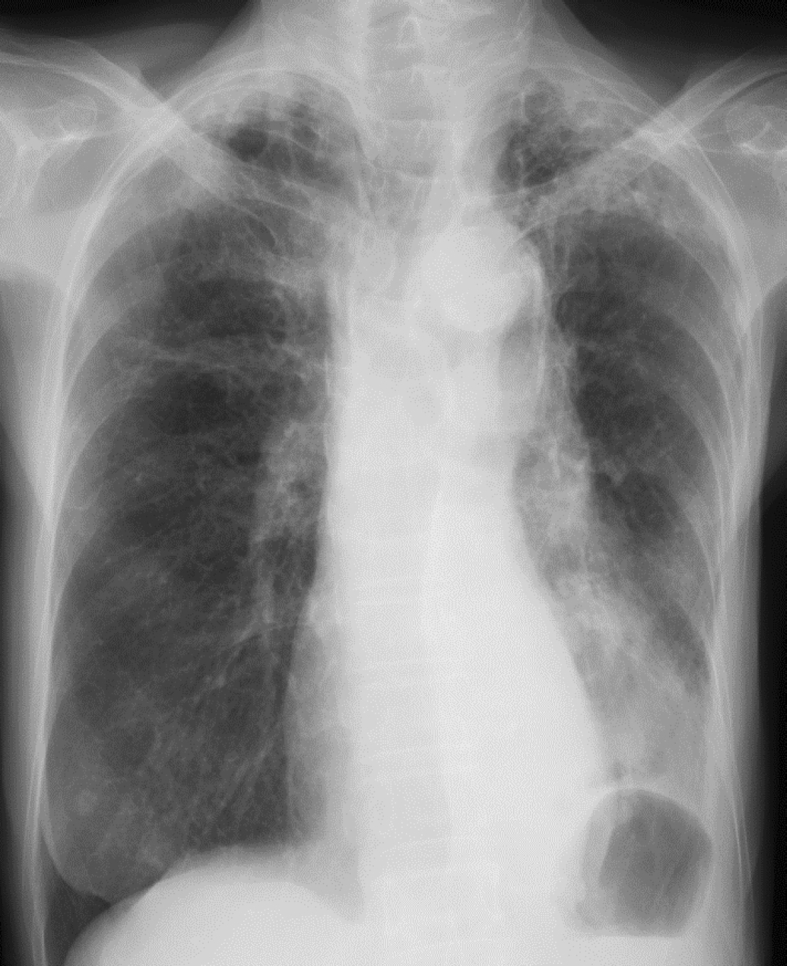

An 80-year-old Japanese female, with a 48-pack years smoking history, presented to a clinic complaining of wet cough and breathing difficulty. She had a past history of tuberculosis, but there was no history or symptoms suggestive of asthma. Chest radiograph revealed left lower lobe collapse (Fig. 1). She was hospitalized after being diagnosed with pneumonia and treated with antibiotics (ampicillin/sulbactam). However, the initial treatment was ineffective, and radiograph findings progressively worsened within weeks. Therefore, she was transferred to our hospital for evaluation and treatment at one month after symptom onset.

Fig. 1.

Chest radiograph on the first visit shows left lower lobe collapse.